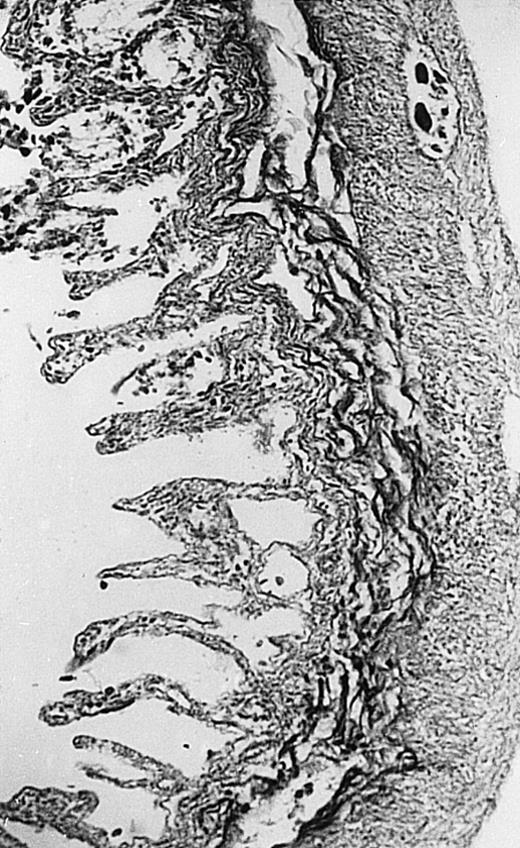

Pathologic findings in the small and large intestine were strikingly different depending on the treatment group. Figure 2A shows a representative pathologic sample from an animal assigned to the control group. Marked thinning of the bowel wall and extensive areas of epithelial cell sloughing was noted. Animals randomized to rhG-CSF treatment had minimal improvement in histologic findings with focal regions of preserved epithelium (Fig2B). Animals randomized to the rhIL-11 group showed substantial improvement with thickening of the epithelial layer and preservation of mucosal cell integrity (Fig 2C). Animals receiving both rhG-CSF and rhIL-11 had the most favorable histologic findings with normal mucosal thickness, minimal inflammatory changes, and preserved tissue architecture (Fig 2D). The composite analysis of the gastrointestinal pathology is provided in Table 1.

Histopathology of small intestinal mucosa cut in transection from an animal in each treatment group (study day 8). The upper panel (row 1) is a low power view (original magnification × 57); the lower panel (row 2) is a high power view (original magnification × 144). Note the diffuse thinning and necrosis of the mucosa with sloughing of intestinal epithelial cells in the control animal (A). There is progressive recovery of the thickness of the mucosa, reduction in inflammatory changes, and improved epithelial architecture with rhG-CSF (B), rhIL-11 (C), and combination therapy with rhG-CSF+IL-11 (D).

The beneficial effects of rhIL-11 in the neutropenic rat model may be mediated by its activity as a hematopoietic growth factor, an antiinflammatory cytokine, or its ability to maintain gastrointestinal epithelial integrity.25,33 The results of the current study would favor rhIL-11 protective effects on the intestinal epithelium as the principal mechanism protection in these animals. Maintenance of the gastrointestinal barrier function should diminish the frequency of gut translocation-derived bacterial infection after chemotherapy-induced myelosuppression and epithelial injury.25 The remarkable preservation of membrane integrity found on the gastrointestinal pathologic samples, the reduced circulating levels of endotoxin, and the reduced bacterial load in organ cultures support a dominant role for epithelial protective effects by rhIL-11 treatment in this animal model.